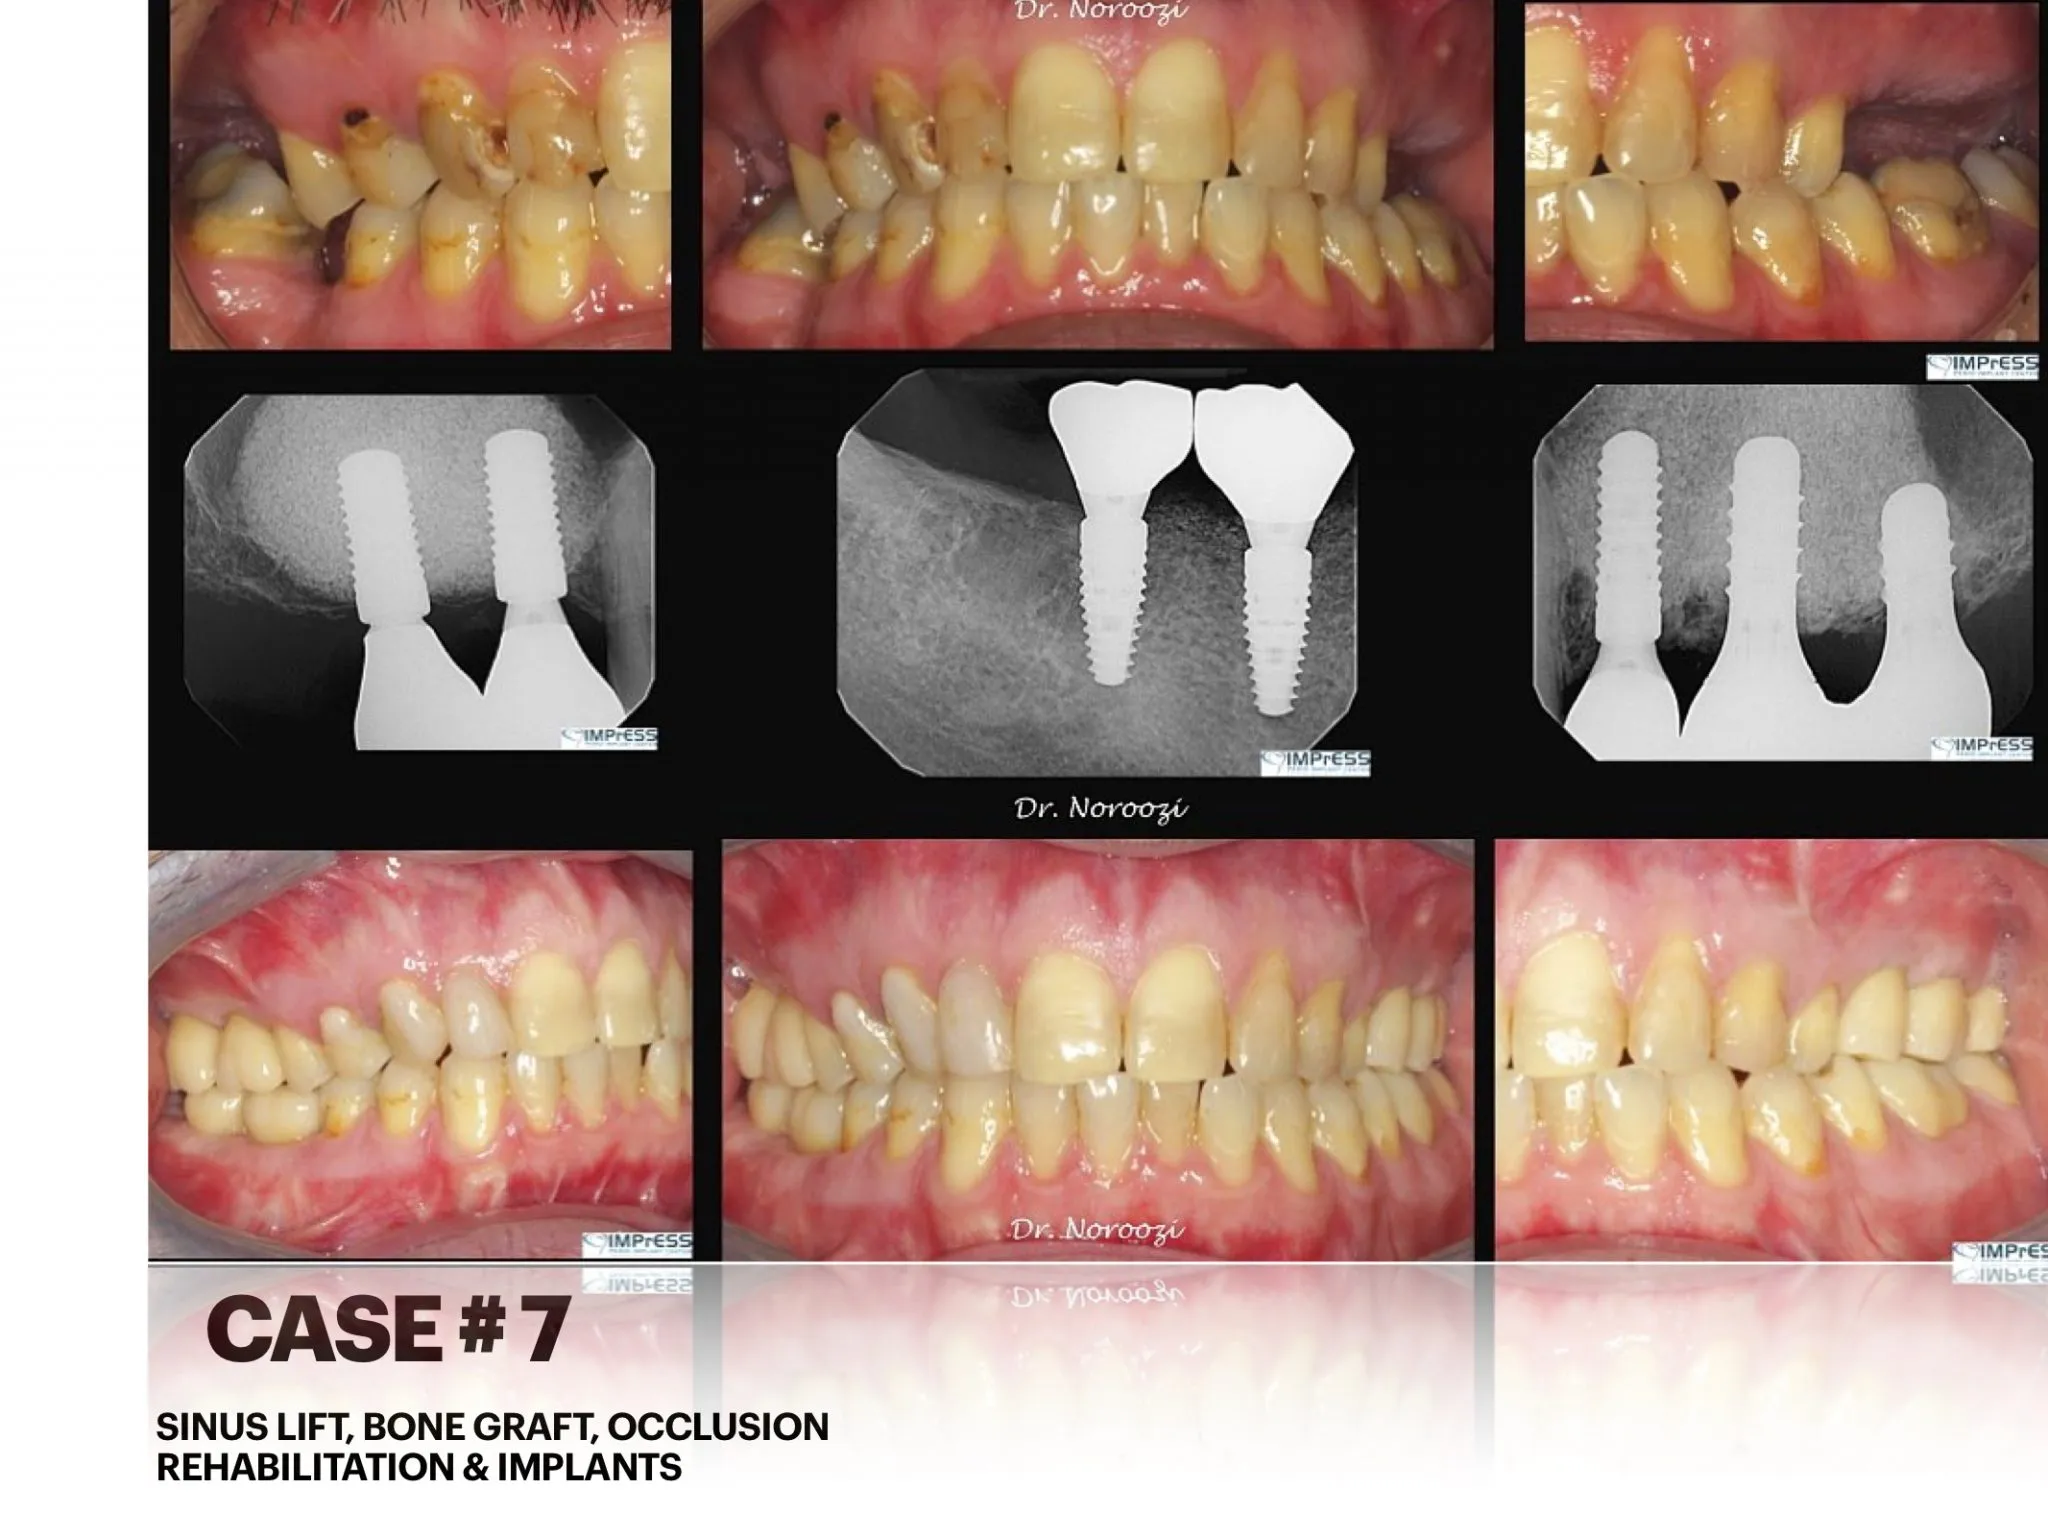

Sinus & Implant Surgery

Dental Implant Centre in Vancouver Burnaby Sinus Lift Dental implant Surgery Dr. Noroozi Implant Specialist IMPrESS Perio Implant Center.001

Sinus Lift, Bone Graft, Implants Dr. Noroozi IMPrESS Perio Implant Center

Sinus Lift, Bone Graft, Dental Implants Surgery and Restoration

Sinus Lift Guided Dental Implant Surgery Vancouver BC Dr. Noroozi Periodontist in Burnaby BC